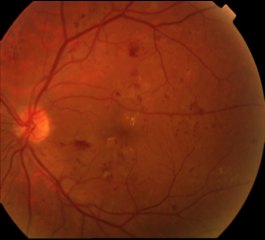

图1 糖尿病视网膜病变的眼底表现

眼科手术以后糖尿病患者出现伤口愈合不良、出血多、角膜水肿、角膜上皮损伤、眼内炎等并发症的危险也相应增加。而糖尿病视网膜病变(以下简称糖网)是糖尿病眼病中最严重的并发症,也是致盲的重要原因之一。在各种致盲眼病中约占8%。我国为糖尿病大国,2003年我国糖尿病的发病率在世界上排第二,目前约有1000万的糖尿病患者并发糖网。在大于40岁的糖尿病患者中,约有40%患有糖网。

糖尿病患者中老年人居多,当他们的眼睛有一些轻微改变时,常常误认为是一种正常的衰退或者白内障。另外,糖尿病视网膜病变一般由视网膜中周部开始,早期对视力没有明显影响,可以没有任何症状,临床上有很多糖尿病患者就是因为没有症状所以从来没有进行过眼科检查,等到出现视力下降再来检查时已经进入了晚期,治疗困难而且效果也不好。也有不少患者是因为出现了眼睛的问题,眼科医生怀疑是糖尿病引起的才去检查血糖,结果发现已经非常严重的并发症了。因此我们建议糖尿病患者不要以是否看得清为标准到眼科就诊。